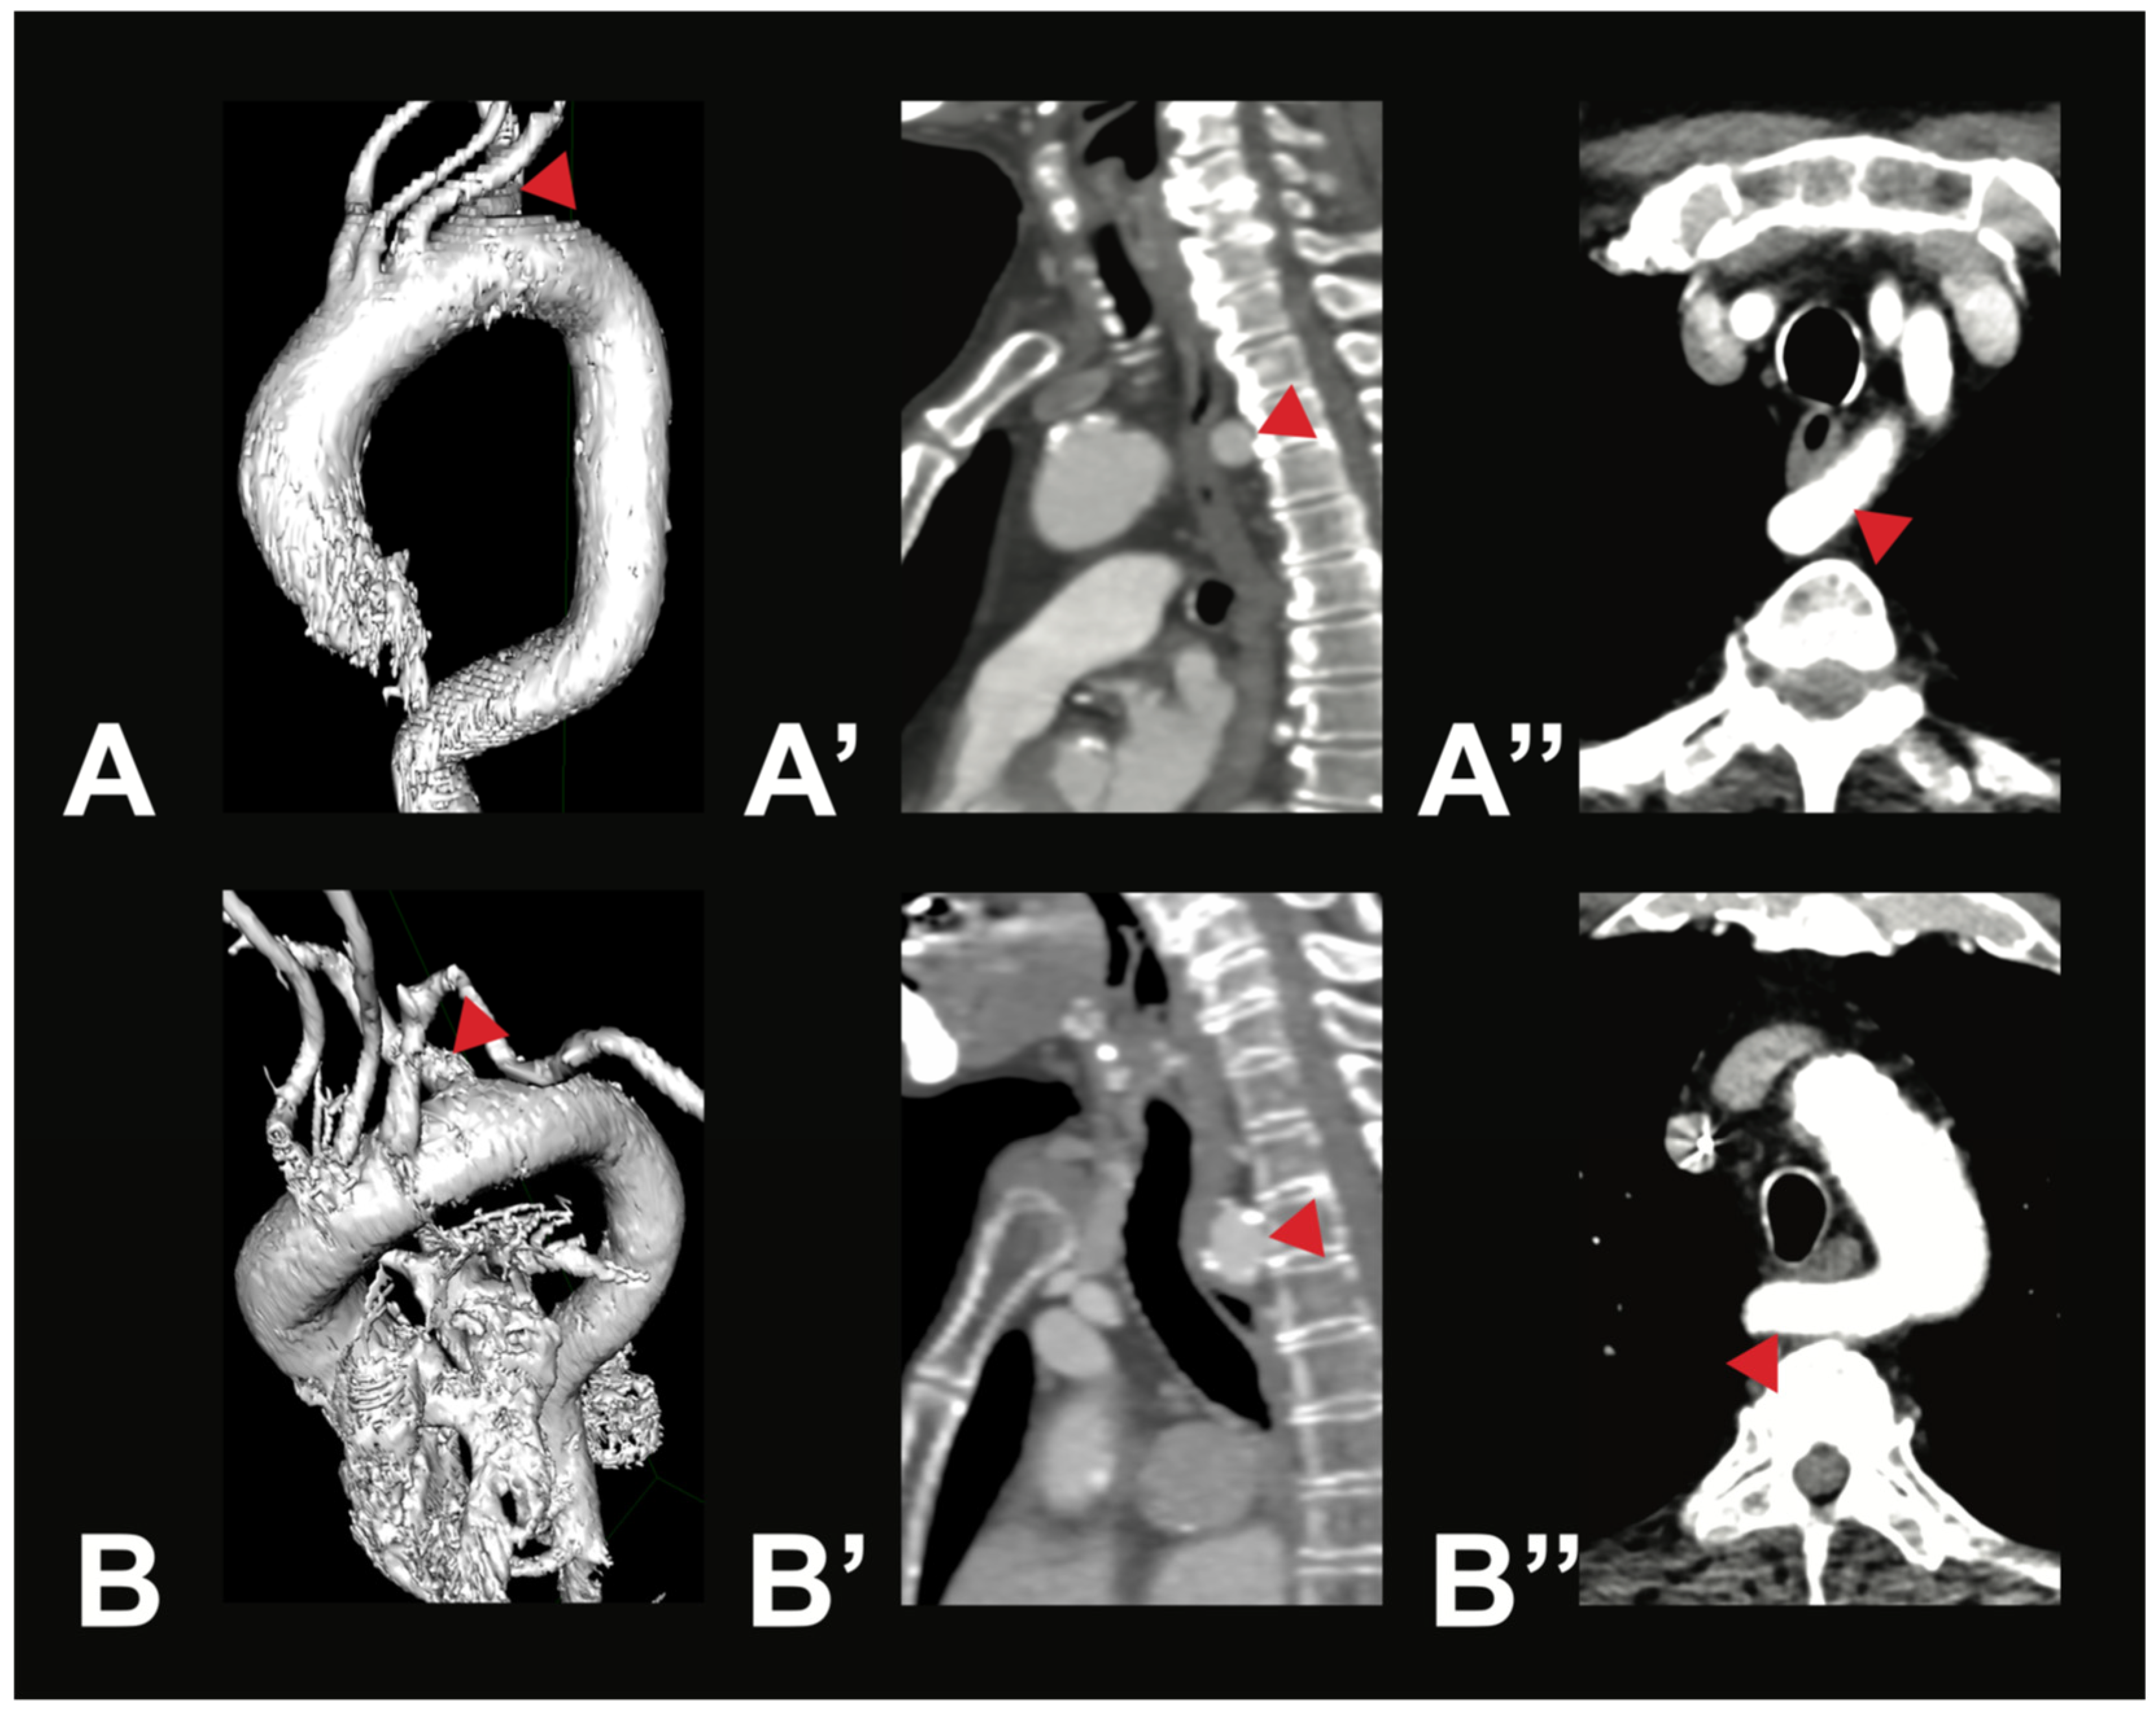

3. Results